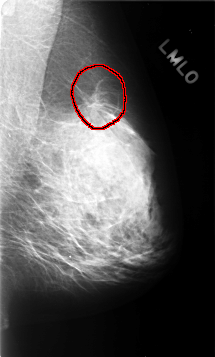

C_0358_1.LEFT_MLO

FILE: C_0358_1.LEFT_MLO.OVERLAY

TOTAL_ABNORMALITIES 1

ABNORMALITY 1

LESION_TYPE MASS SHAPE IRREGULAR MARGINS SPICULATED

ASSESSMENT 5

SUBTLETY 5

PATHOLOGY MALIGNANT

TOTAL_OUTLINES 1

BOUNDARY